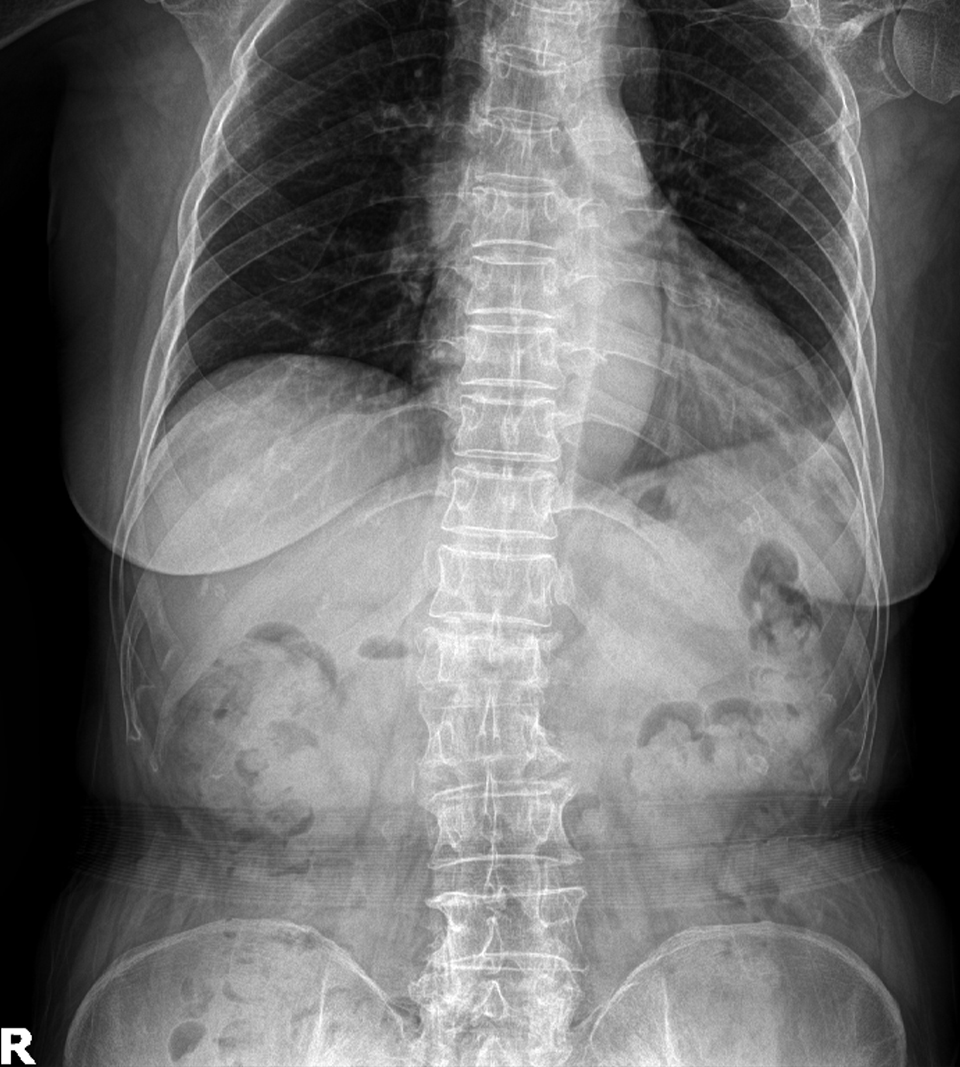

Compression Fracture

<수술후>

- 환자 동의하에 게시된 이미지입니다.